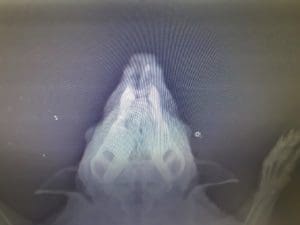

Not all of our hedgehogs are easily treated, but the team never give up. Last year, a hedgehog was admitted to us having difficulty breathing. He was given medication by our vet, and was monitored closely. His condition was up and down for months, so this year the decision was made to x-ray him. From this we found that a foreign body in his nasal cavity was the cause of his problems. Now he is finally showing signs of improvement, and will be released very soon.